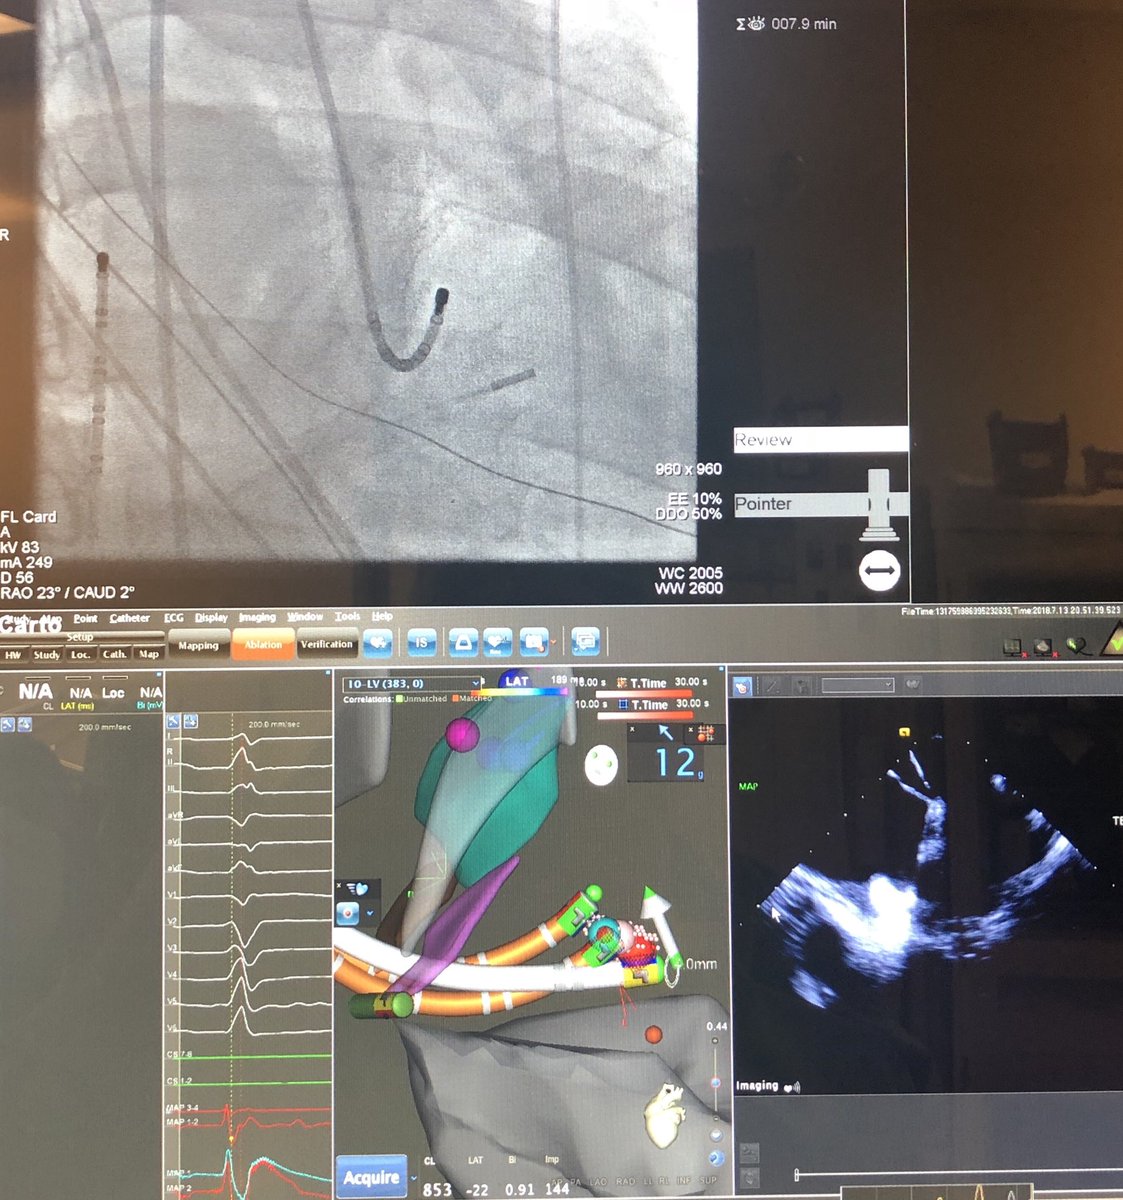

#ICEeyes and #HDmapping for ablation of papillary muscle VAs. Anatomical and electrophysiological information for a successful treatment. Case 1 (intial experience with NavX PM-mapping)

thegellergroup's tweet image. #ICEeyes and #HDmapping for ablation of papillary muscle VAs. Anatomical and electrophysiological information for a successful treatment.

Case 1 (intial experience with NavX PM-mapping)